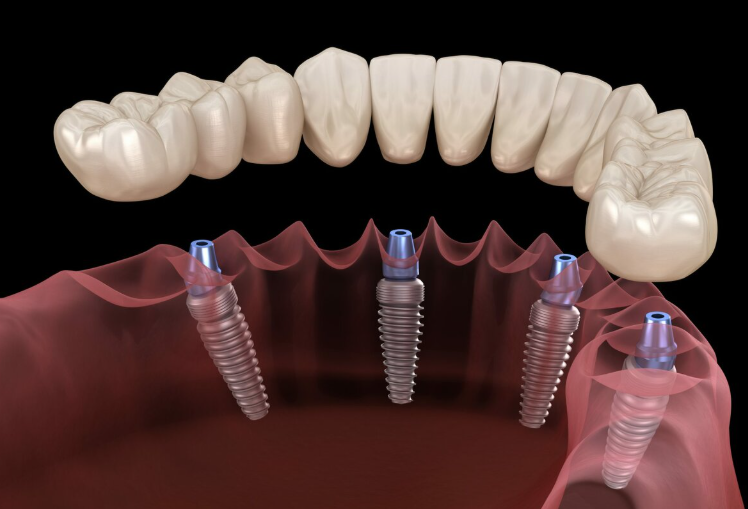

جسور على زرعات

تعويض عدة أسنان بجسور مدعومة بزرعات

All-on-4

استعادة الفك الكامل بأربع زرعات موضوعة بشكل استراتيجي

All-on-6

ثبات معزز بست زرعات لدعم الفك الكامل